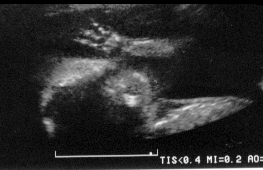

Here are my darling feet

Waving Hi to Mommy, Daddy and Big Sister!